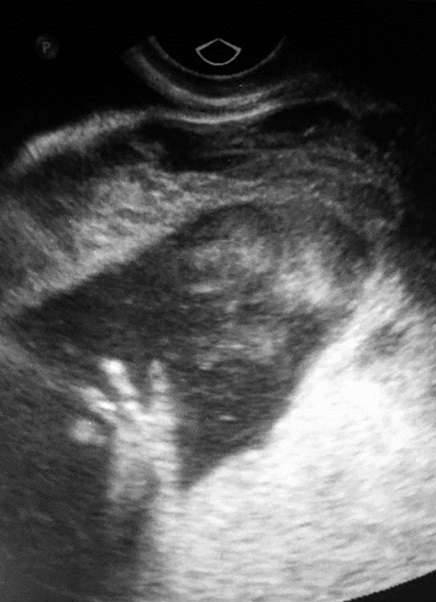

▼2016年2月时,琳赛腹中的女儿欧玛拉(Omara)恰巧18週大,但当他们喜悦地準备迎接这个新生儿时,医生却在例行的超音波检查告诉她,宝宝的脖子上出现了一个肿块。

▼超音波显示宝宝的脖子上有个异样突起,医生认为这是一种谜样的「畸胎瘤」(teratoma),事情的真相只能透过核磁共振成像来进一步推测。